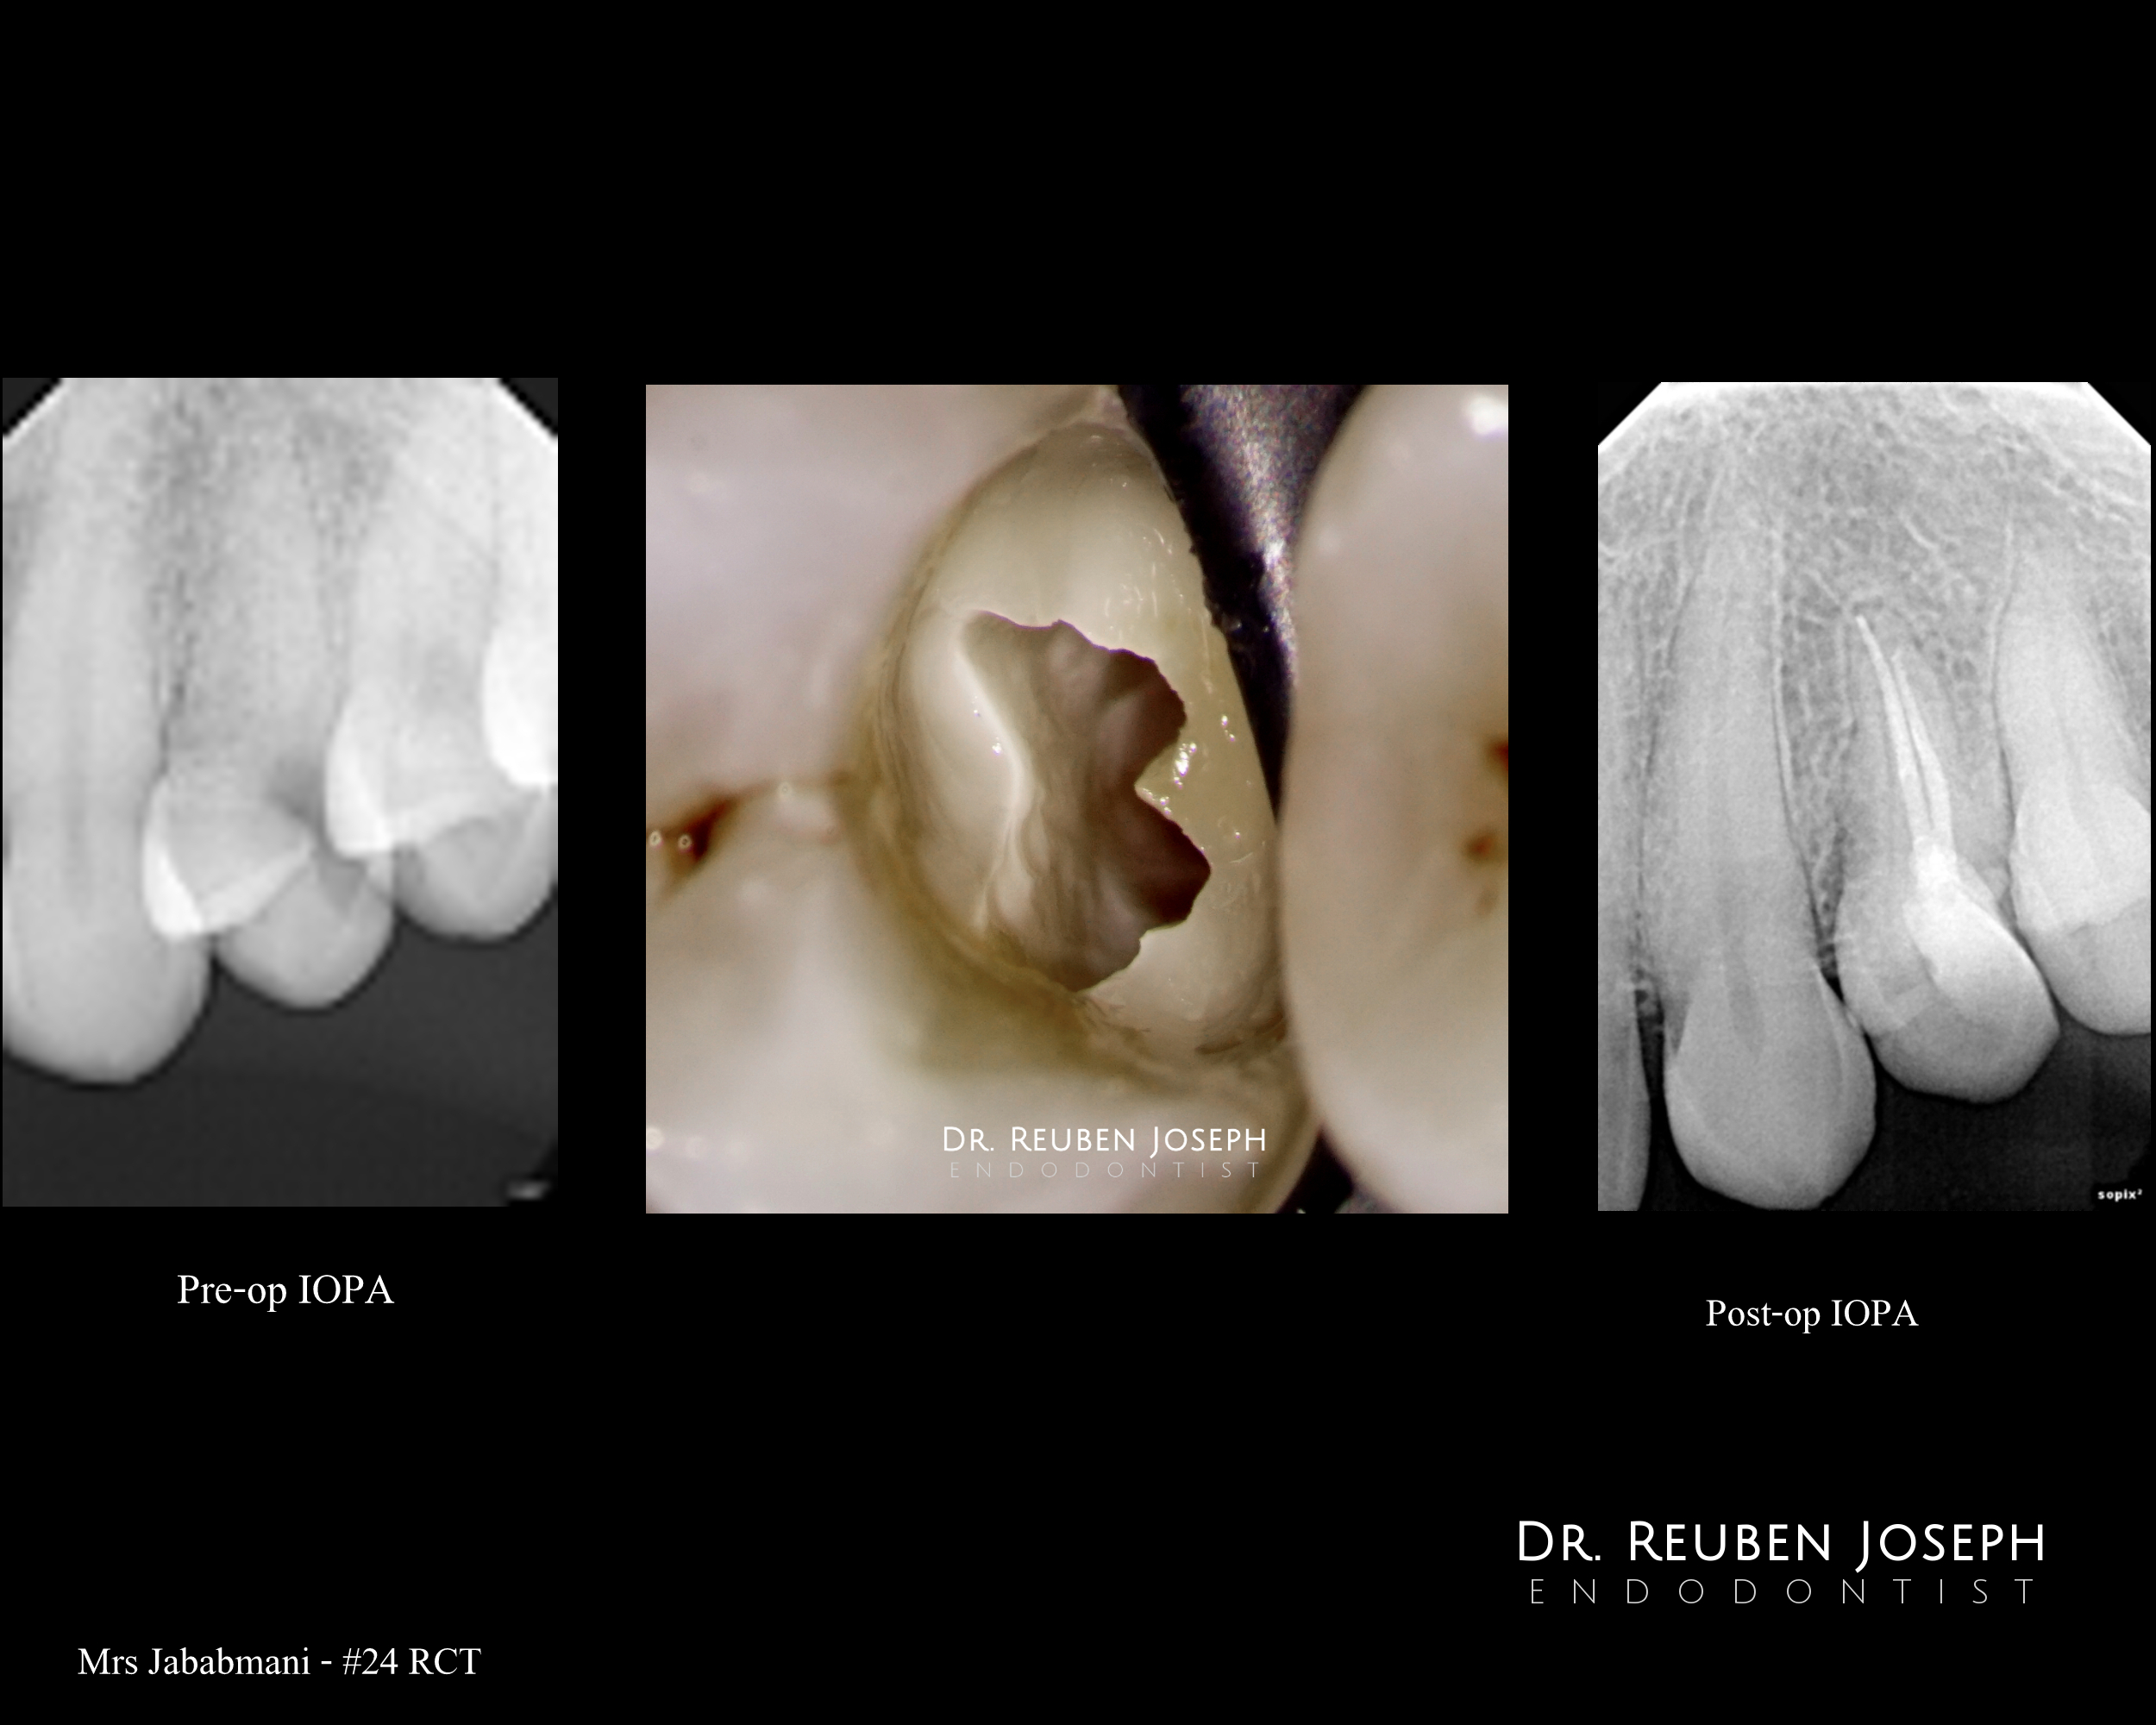

Nothing  special. A few premolars i got to treat recently with access cavity designs specific to what the clinical scenario demanded.

Case 1